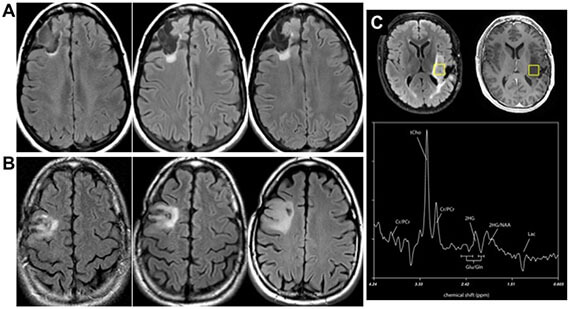

- R21 “Diagnosis of low-grade glial tumors using 11C glutamine isotopomers” (PIs Villanueva-Meyer, Wilson). 2021.

Detection of low-grade glioma and chondrosarcoma via isocitrate dehydrogenase mutants (IDHm)

The Wilson laboratory is developing metabolism-targeted methods to identify tumors harboring IDHm, either (1) based on consumption of tumor-relevant metabolites or (2) direct detection of the IDHm enzyme via modification of known inhibitor structures. These tools will significantly impact the diagnosis and treatment of low-grade glioma and other lesions. These studies are performed in collaboration with the laboratory of Dr. Pavithra Viswanath and clinical collaborator Dr. Javier Villanueva-Meyer.